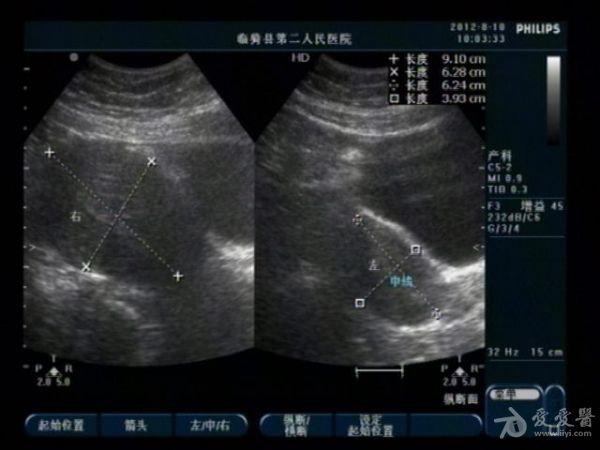

典型双子宫图像

前几天,我们科来了一位老病号,一年前剖腹产患者。当时手术证实“双子宫”今天超声图像可见一大一小两个子宫,右侧较大拟诊“子宫内膜异位症”。患者有经期腹痛史。

患者今年29岁,现生有一孩,就是剖宫产那个孩子。具体是那个子宫患者也不清楚,因在外地做的手术我们未能得到准确资料。患者近几个月来有明显的痛经史